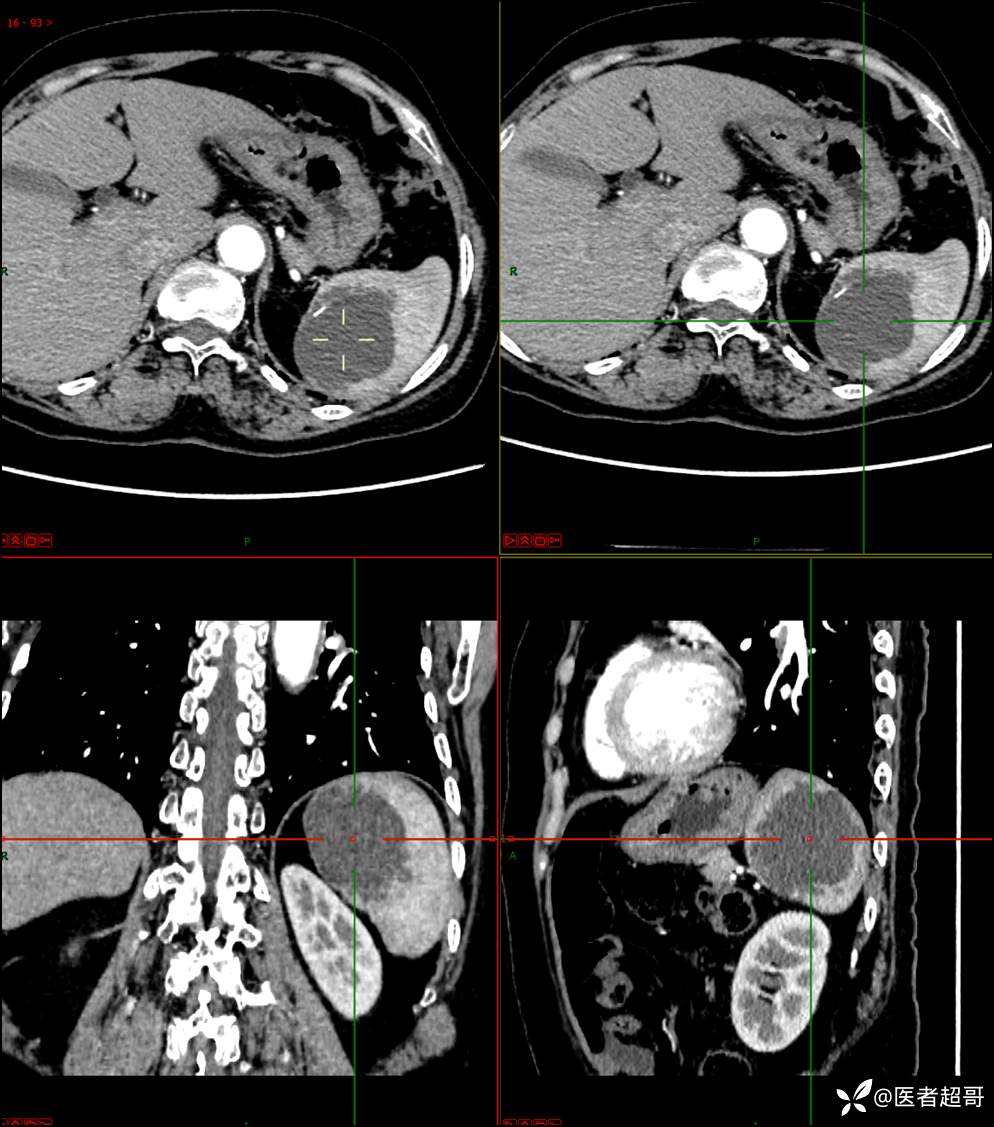

【影诊笔记598】脾脏占位03,脾脏囊性占位,回帖即可查询病理,请分析!

现病史:患者9天前于市人民医院查体时发现脾脏肿物,未行处理,后于我院门诊查,上腹部CT平扫+强化:脾脏占位,考虑良性,囊肿?脉管源性病变?患者诉平素无异常不适。现患者为求进一步诊疗,门诊遂以“脾肿物”收入院。患者自患病以来,神志清,精神可,饮食、睡眠可,大小便正常,体重未见明显变化。